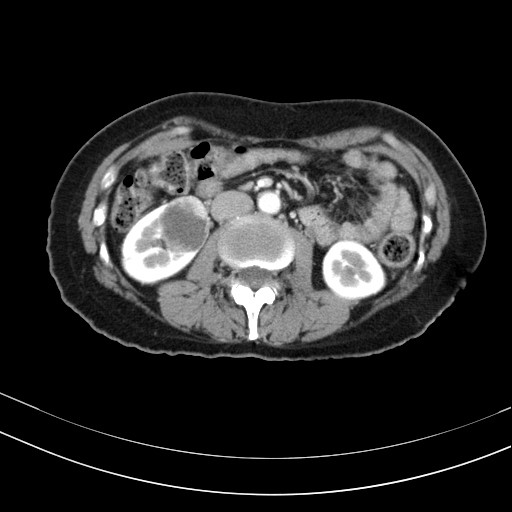

37¼¼ ¿©¼ºÀÌ Àü½ÅÇÇ·Î ¹× µÎÅëÀ» ÁÖ¼Ò·Î ³»¿øÇÏ¿´´Ù.  Æò¼Ò °Ç°­ÇÏ´ø ºÐÀ¸·Î¼­ ¾à ÇÑ´ÞÀüºÎÅÍ ¸Ó¸®°¡ ¹«°Ì°í ÇǷΰ¨ÀÌ À־ ³»¿øÇÏ¿´´Ù.  Ưº°ÇÑ °¡Á··ÂÀ̳ª º´·ÂÀº ¾ø¾ú´Ù. Á¤»ó üÇüÀ̾úÀ¸¸ç Ç÷¾ÐÀÌ 170/110mmHg ·Î  °íÇ÷¾Ð ¼Ò°ßÀÌ °üÂûµÇ¾ú´Ù.  °íÇ÷¾ÐÀÇ ¿øÀÎÀ» ã¾Æº¸±â À§ÇÏ¿© º¹ºÎÃÊÀ½ÆÄ, °©»ó¼± ÃÊÀ½ÆÄ , Ç÷¾×°Ë»ç µîÀ»  ½ÃÇàÇÏ¿´´Ù.  º¹ºÎÃÊÀ½ÆÄ°Ë»ç»ó ¿ìÃø ½ÅÀå¿¡ Àú¿¡ÄÚÇü °áÀýÀÌ °üÂûµÇ¾ú´Ù(±×¸²1).  Á¾¾çÀ» È®ÀÎÇϱâ À§ÇÏ¿© ½ÃÇàÇÑ º¹ºÎCT¿¡¼­µµ ¿ìÃø½ÅÀå¿¡ 5cm Å©±âÀÇ Á¾±«°¡ °üÂûµÇ¾ú´Ù(±×¸²2). ½ÅÀåÁ¾¾çÀ¸·Î ÀÇ½ÉµÇ¾î ¼ö¼ú·Î ½ÅÀåÀ» ÀûÃâÇÏ¿´À¸¸ç Á¶Á÷°Ë»ç»ó ½ÅÀå¾ÏÀ¸·Î È®ÁøµÇ¾ú´Ù.  ¼ö¼úÈÄ Ç÷¾ÐÀº 100/60 À¸·Î Á¤»óÈ­µÇ¾î Ç÷¾Ð¾àÀº Áß´ÜÇÏ¿´´Ù.

÷ºÎÆÄÀÏ 2 : RCC_CT.jpg